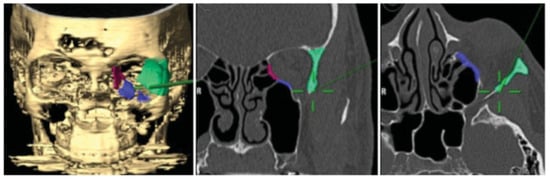

Similar to the first case, DICOM data from the CT study were utilized to plan a two-wall (lateral wall and orbital floor) decompression on the right side and a three-wall decompression (lateral wall, floor, and medial wall) on the left side (Figure 8).

Figure 8. Axial, coronal, and sagittal views with 3D reconstruction for patient 2, showing the preoperative plan for the left-sided, three-wall orbital decompression surgery.